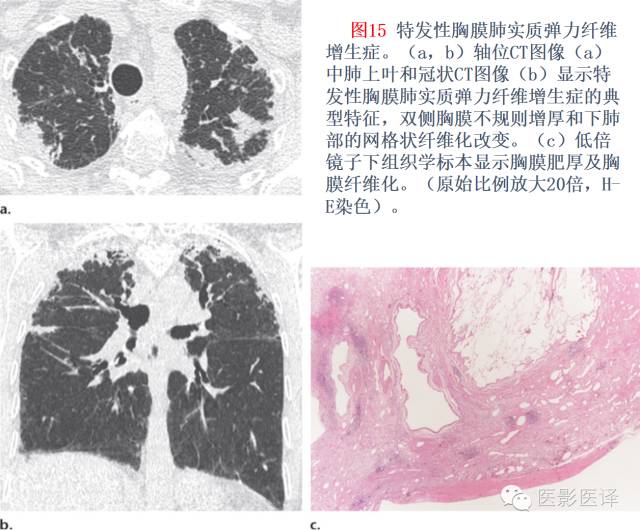

2、特发性胸膜间质弹力纤维化 医学百科网 | YxBaike.Com

特发性胸膜间质弹力纤维化是罕见病,富含弹力纤维,病变涉及胸膜及胸膜下肺实质,主要分布在上叶肺组织。60%的病例疾病会有所进展,40%的病人死于此病。

CT特征–特发性胸膜间质弹力纤维化的CT表现是显而易见的,不规则的胸膜增厚,在靠近上肺野区域可见混有纤维化改变,这是其“易于”,合并大部分上叶体积萎缩(结构扭曲,牵拉性支气管扩张,肺门上抬)(表1:图2,15)。Reddy等研究结果表明CT纤维化的特征与胸膜肺实质的改变距离很大,(例如,在中、下肺野),12个病例中5例(42%)已阐述远离肺胸膜(例如中下肺野)的纤维化CT表现,大多数肺纤维的异常表现则是NSIP的CT残留,虽然肺活检的结果揭示了这些病例为普通型肺间质纤维化。

纵向评估—少有数据对特发性胸膜间质弹力纤维化进行纵向评估,系列CT影像研究表明关于胸膜肺实质的改变是稳定的,少有进展。然而,在几个月内也已经有人阐述了显著的进展。

鉴别诊断—鉴别诊断一般包括家族性肺纤维化,结缔组织病(尤其是强直性脊柱炎),纤维化结节病和慢性过敏性肺炎,然而,明显的尖部病变优势和增厚的胸膜将有助于鉴别特发性胸膜间质弹力纤维化,虽然一些慢性过敏性肺炎的病例也可能有类似相同的表现。 医学百科网 | YxBaike.Com

然而,明显肺尖部胸膜帽与其胸膜增厚通常会有助于区分特发性胸膜肺实质弹力纤维增生症与其他实性病变,尽管一些慢性过敏性肺炎也会有相似表现。